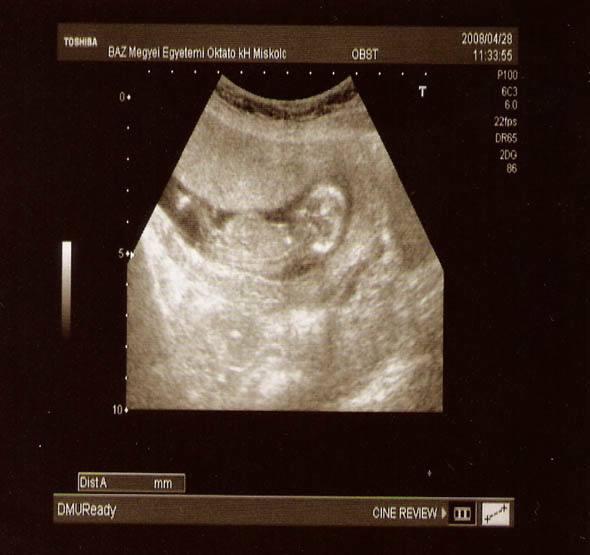

Mi tegnap voltunk a 12. hetes uh-n, hát nagy élmény volt, mint mindig! persze minden rendben, bpd-je 22 mm-es, nyaki redő 1,8 mm! Az uh-s nővel tök jól összehaverkodtunk, (persze lehet, hogy a nagy tábla mogyis csoki tette meg a hatást... :wink: ) így mindent tök jól megmutogatott, a férjem is bent volt, és nagyon ficánkolt! Fel-le húzogatta a térdét! Nagyon édes volt! A doki most meg sem vizsgált, (aminek én örültem...) ha nincs panasz, akkor nem tartja szükségesnek az állandó kézi vizsgálatot.....ja és a pénzt sem fogadta el....Szóval eddig minden oké, vele is! :)

Na, és a sztárfotó.........a hátát mutatja.....szépen látszik a gerince, meg a popója, felhúzott lábbal...! remélem ti is látjátok!